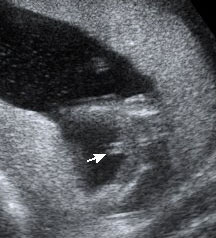

Ladies, went in for our 16 week ultrasound and came out this photo. Just wanted to get other moms opinions. it looks nothing like my sons did (second photo) and his was done at 16 weeks as well. up close it looks like an owl haha